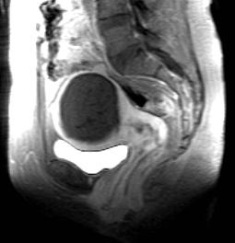

| 47 岁女性,伴有 严重经期出血和盆腔疼痛症状。冠状位[A]和矢状位[B]的 T2 加权磁共振成像显示子宫增大范围内存在中等信号病变。[C] 轴位 T1 后处理图像显示子宫内有强化肿块,边缘不规则。 | ||

影像学检查结果: 质地较硬的肿块,边缘不规则,T2 期呈中等至较高强度,T1 期呈高信号(提示出血) 没有任何标准能够将退化的子宫肌瘤与平滑肌肉瘤区分开来。

罕见情况:<1% 的患有子宫肌瘤的女性(患病风险为) (0.04 至 0.13%)

症状 盆腔疼痛、出血、可触及肿块

建议: 与之前的影像检查结果相比;生长速度极快(在 3 至 6 个月内增长了一倍)……这很令人担忧!